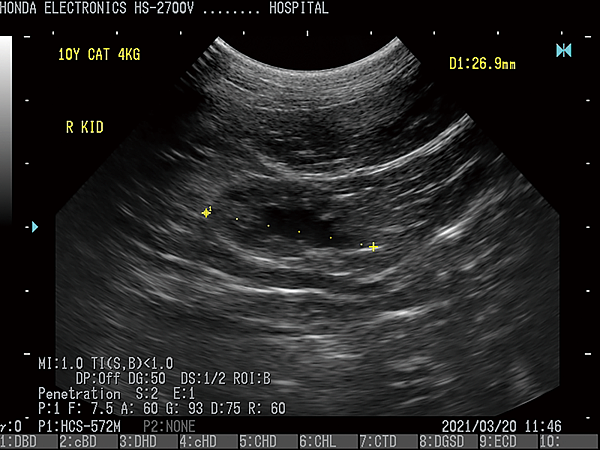

(動物用)(獸醫)

- 通過H-res獲得清晰豐富的單色圖像

HONDA獨創的圖像增強技術 H-res(我們的分辨率技術)

多年來超聲波技術的發展,結晶為“ H-res”圖像增強技術。

可以通過針對每種應用和探頭調整“ H-res”參數來獲得最佳圖像。

* 分辨率可在較淺的區域可視化精細的組織結構。* 穿透力可以在更深的器官中顯現出良好的分辨率。* 邊界可視化骨骼以進行觀察。* 清晰度降低了血管中的噪音。* 溫和會降低圖像增強效果。* OFF具有直接的超聲圖像。

HS-2700支持CFM(彩色血流向)和PD(功率杜普勒)模式。